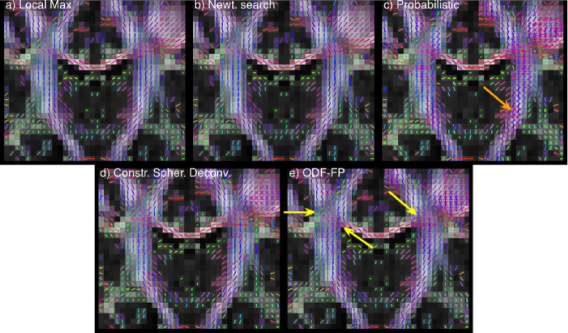

Refer to caption

Figure 10: Fiber directions are identified by local maximum search (DSIStudio, a), Newton search (MRtrix3, shpeaks, b), probabilistic estimation (FSL, bedpostx, c), constrained spherical deconvolution (MRtrix3, dwi2fod msmt_csd, d) and ODF-Fingerprinting (ODF-FP, e) in a coronal slice of a whole brain in vivo dataset. Example areas where ODF-FP performed better are indicated with a yellow arrow; an example area where spurious fibers are detected are indicated with an orange arrow.

Figure 11: Fiber tractography of the corticospinal tracts (a,e,i,m,q), the left arcuate fasciculus (b,f,j,n,r), the optic radiations (c,g,k,o,s) and the forceps minor (d,h,l,p,t) in a whole brain RDSI dataset. Fiber directions are identified by local maximum search (DSIStudio, a-d), Newton search (MRtrix3, shpeaks, e-h), probabilistic estimation (FSL, bedpostx, i-l), constrained spherical deconvolution (MRtrix3, dwi2fod msmt_csd, m-p) and ODF-Fingerprinting (ODF-FP, q-t).

Fiber tractography on a whole brain in vivo dataset shows that the fiber directions identified by ODF-FP (Fig. 10) allow the algorithm to improve results (Fig. 11). Fiber bundles generated with ODF-FP input probe the expected anatomical extent of the tracts in contrast to the fiber bundles based on ODF maximum search methods and CSD, in particular for the Corticospinal tract. The tendency of probabilistic methods to derive erroneous fiber directions (e.g. Fig. 6, ODF 1,4) produces more spurious tracts (Corticospinal tract, Arcuate Fasciculus and Optic Radiation in particular).